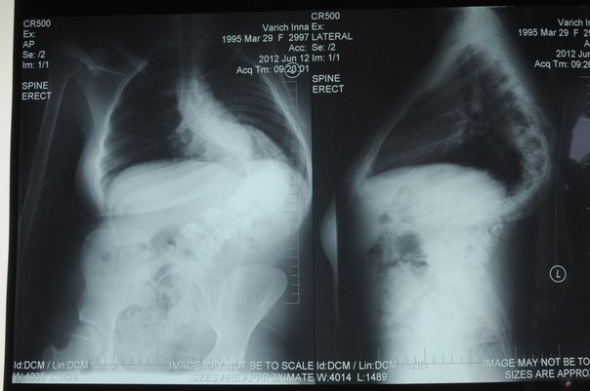

17-річній Інні Варич з міста Умань на Черкащині терміново потрібна операція із виправлення хребта. У неї сколіоз найважчого 4 ступеню, хребет викривлений вже на 95 градусів. Через це почалися проблеми із серцем та внутрішніми органами. Ситуація ускладнюється тим, що у Інни з дитинства немає лівої руки. Якщо не зробити операцію дівчинці загрожує інвалідне крісло.

"Ми постійно відвідували лікарів в Умані, Інні робили масажі, проте біль не проходив, - розповідає мама Інни Марина Варич. – Але нам за 17 років ніхто не сказав, що можна зробити операцію. З кожним днем Інні все важче, серце стискається під тиском хребта. Коли дізналися, що такі операції роблять в Охматдиті, то не задумуючись поїхали туди. Після всіх обстежень нам призначили операцію на 20 вересня. Але потрібно купити імплантат, який вирівнюватиме хребет, до середини серпня. Він коштує 35 тисяч гривень. Таких коштів у нас немає. Ми робимо все аби зібрати гроші, бо це єдиний шанс для нашої дитини."